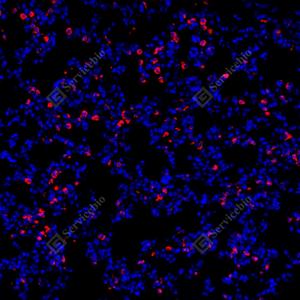

IF检测CD68蛋白(货号 GB113109)(红色). 样品: 小鼠免疫脾, 4%多聚甲醛 (货号G1101) 固定12-24小时. 抗原修复: Tris-EDTA抗原修复液(pH 9.0) (G1203), 98℃, 20分钟. 封闭: 3% BSA(货号GC305010)的PBS溶液, 室温孵育30分钟. —抗: 1: 200稀释, 4℃ 孵育过夜. 二抗: Cy3标记山羊抗兔IgG (H+L) (货号GB21303), 1: 300稀释, 室温孵育1小时. |